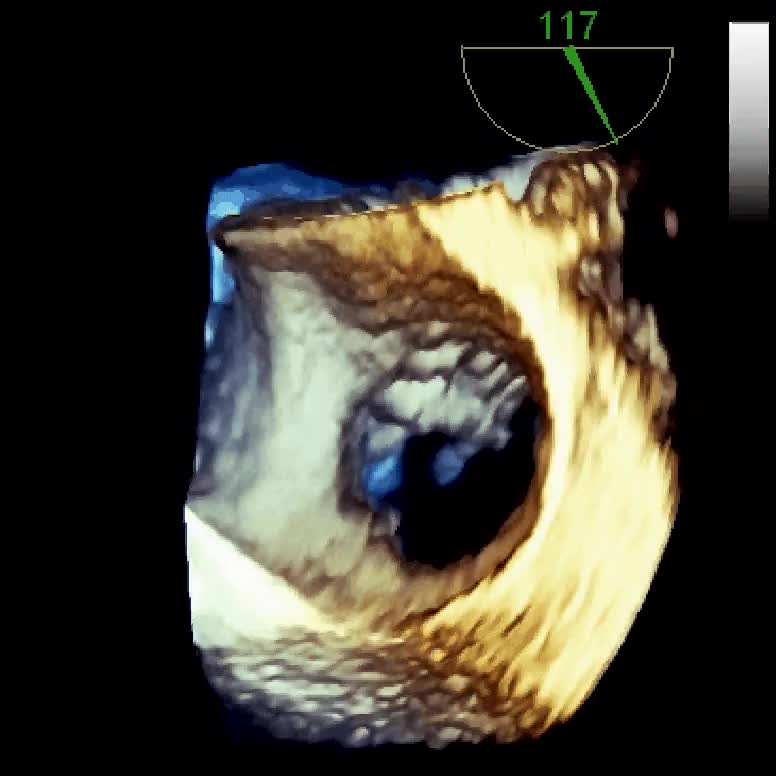

Titolo:

Distacco di protesi meccanica mitralica da endocardite infettiva con severo rigurgito paraprotesico

Autore:

Manfredo Cerchiello